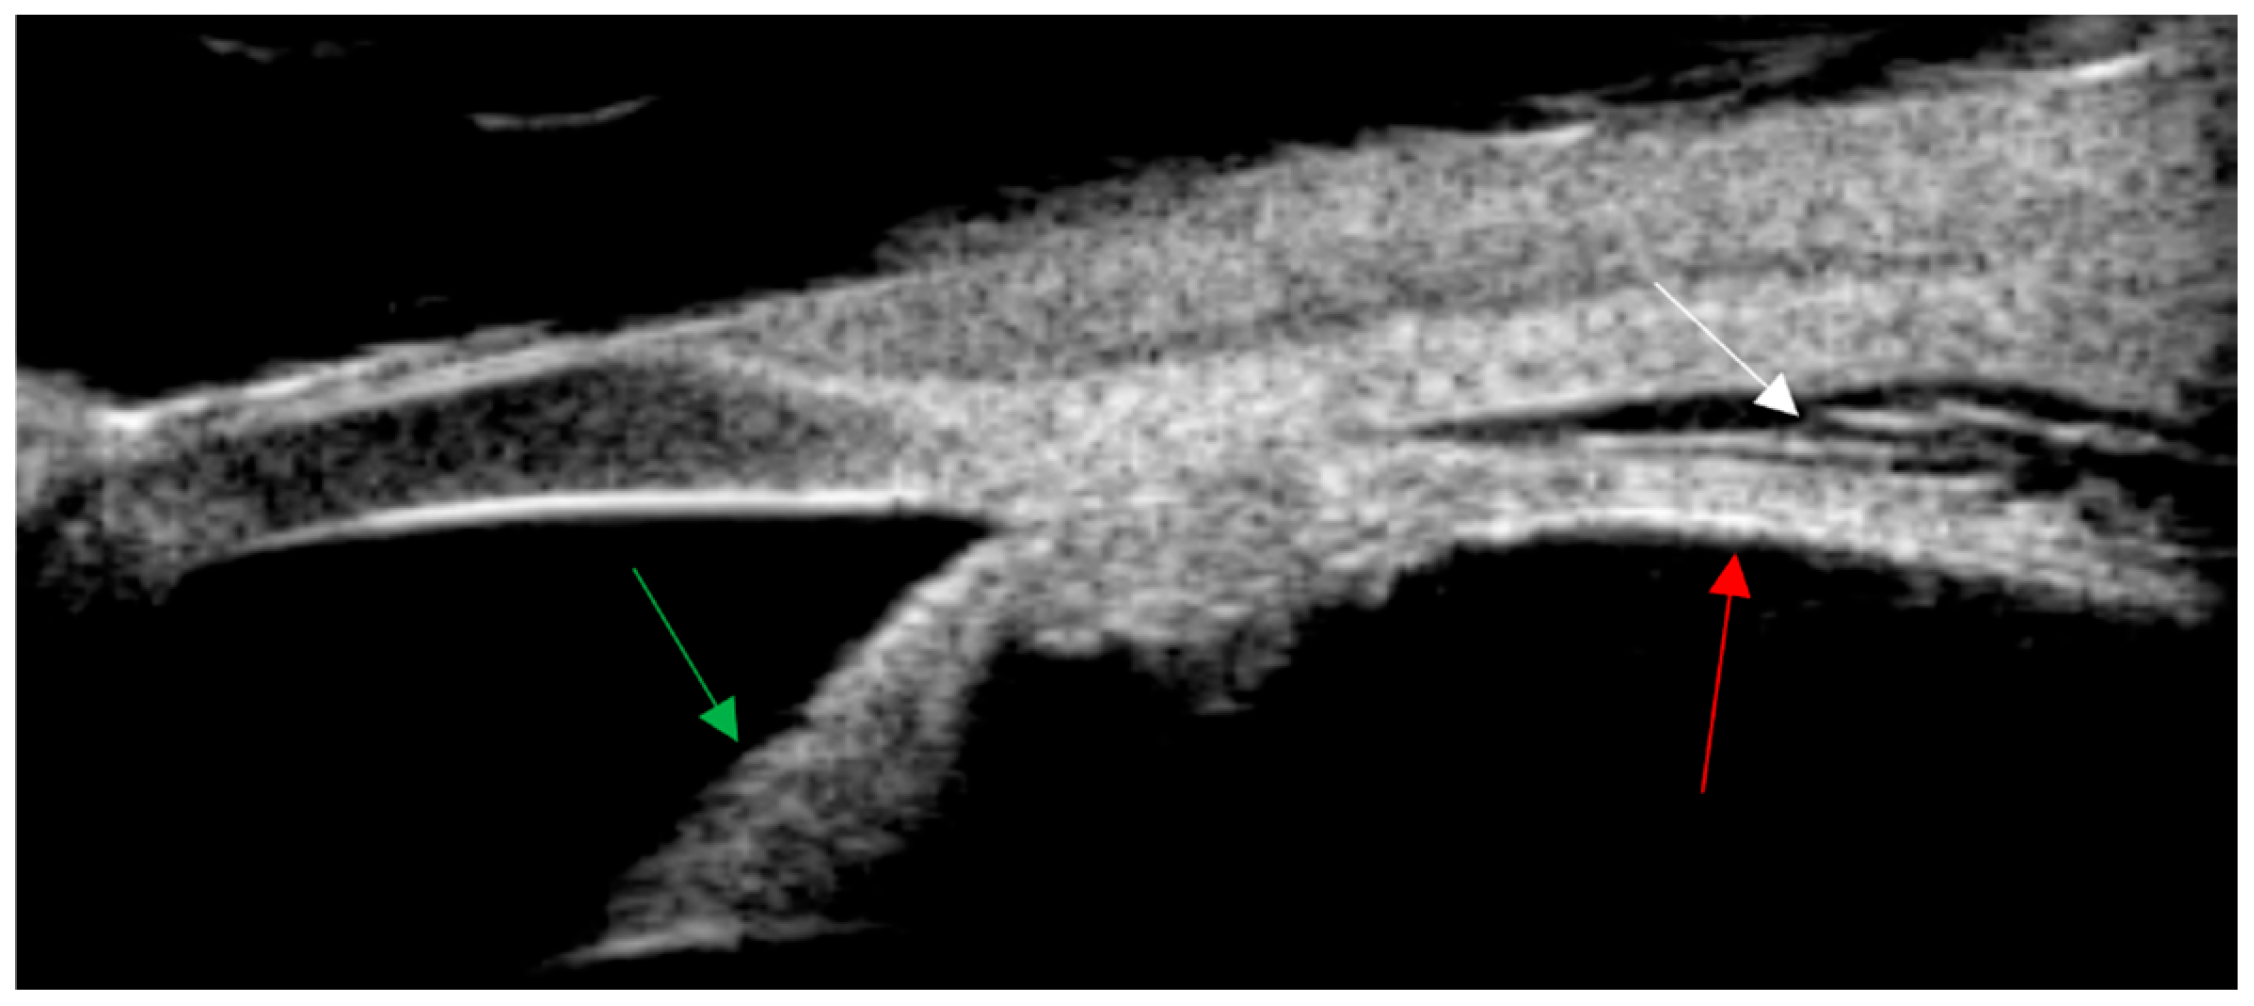

After 25 days of medication treatment, the boundary of the optic disc was clearer than before, and the retina was reattached. There was no significant change in the yellow–white exudate under the retina above the temporal side of the optic disc. Point-like exudates appeared under the peripheral retina, and the vitreous inflammation, was reduced. Reports from the literature indicate that rifampicin, ciprofloxacin, gentamicin, azithromycin, and compound sulfamethoxazole are all effective against cat scratch disease [1,2]. It is recommended that gentamicin be used preferentially for severe cases. In clinical treatment, antibiotics are usually used in combination. It is recommended to use drugs such as aminoglycosides, azithromycin, and quinolones. Clinical treatment generally requires more than 2 weeks. If necessary, lymph node puncture, pus aspiration, or resection in the affected area can be considered [1]. The effectiveness of steroids is uncertain. This patient was treated with rifampicin eye drops and erythromycin eye ointment topically in the eye, and rifampicin, azithromycin, and steroids systemically. The retinal detachment in the left eye was reattached, and the enlarged lymph nodes on the left thigh subsided. However, the huge exudate under the retina in the macular area could not be absorbed, resulting in a final visual acuity of only 0.03. The explanation of the arrows: The white arrow is the yellow–white mass under the retina, the green arrow is the flattened retina, and the red arrow is the yellow–white point-like exudate.